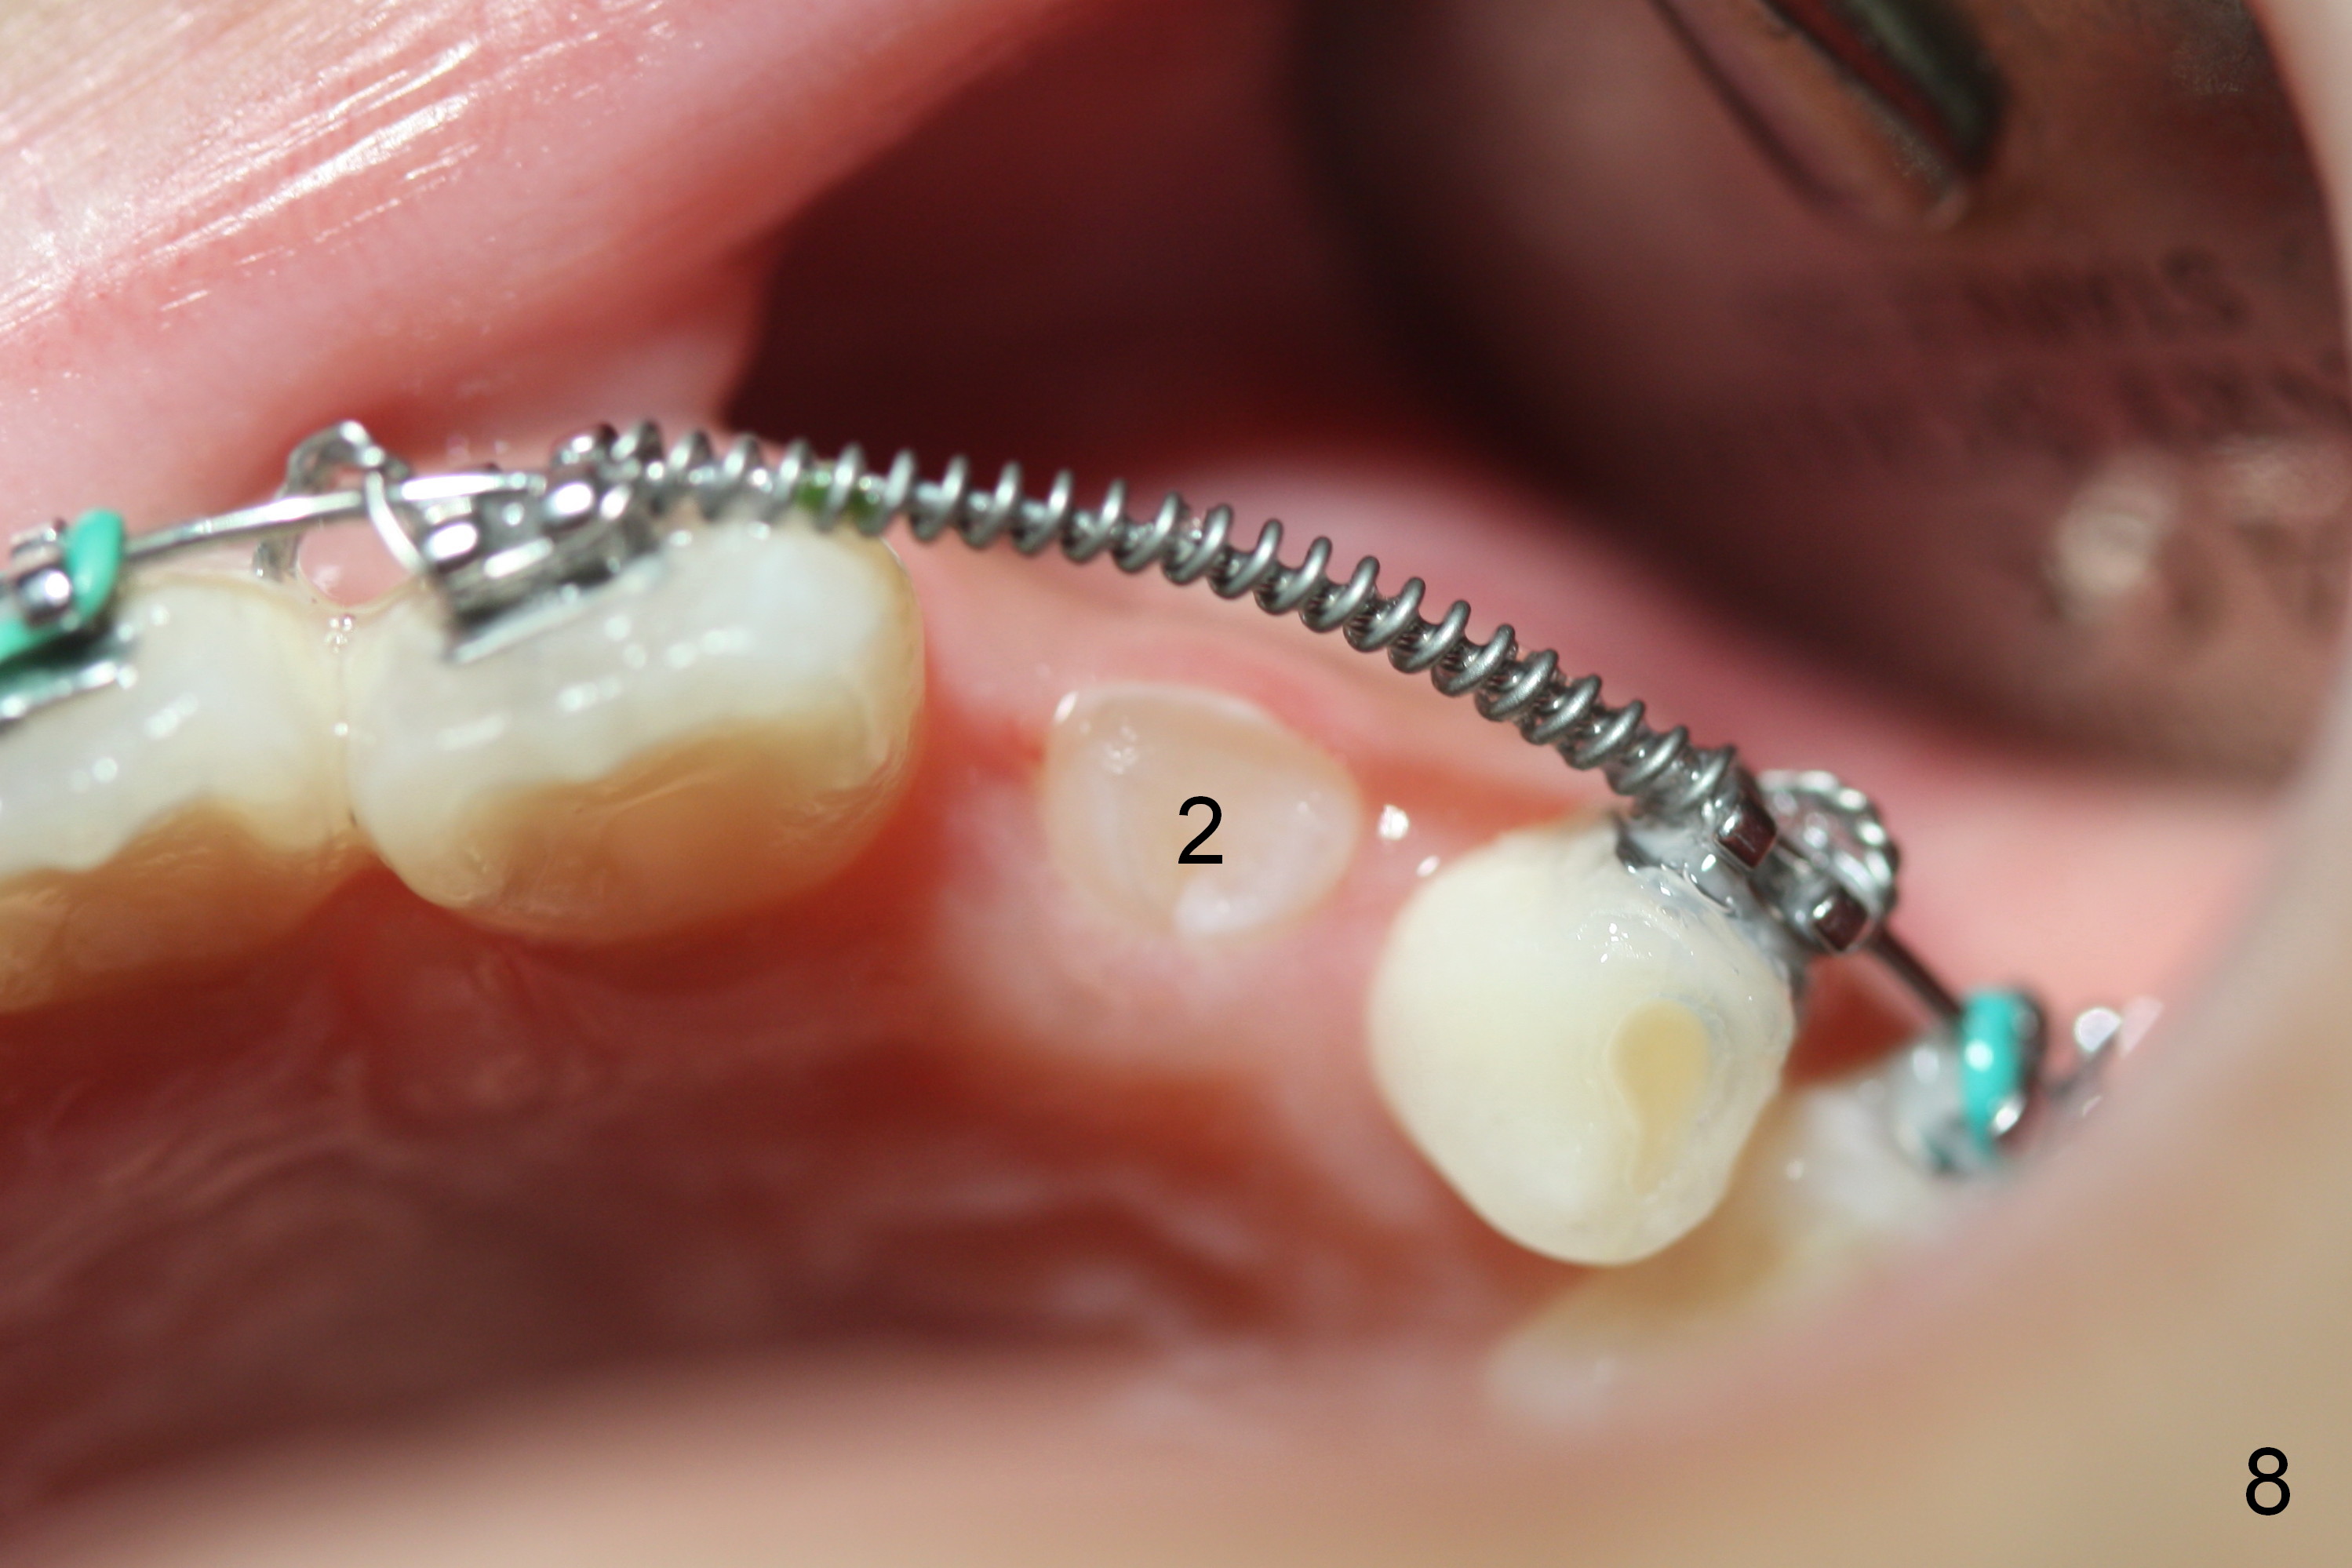

Space has been created for UL2 3.5 months post initial banding (Fig.7). Gingivectomy is performed with Diodie Laser over the incisal edge of the unerupted tooth. One week later, UL2 is erupting (Fig.8,9). Open coil spring is removed. Class II retraction is placed with elastic to correct anterior cross bite. UL6 eruption is still incomplete, due to lack of constant retraction. It is difficult to place band for the incompletely erupting tooth. Otherwise, face mask is used for more efficient retraction. The patient happens to travel abroad.